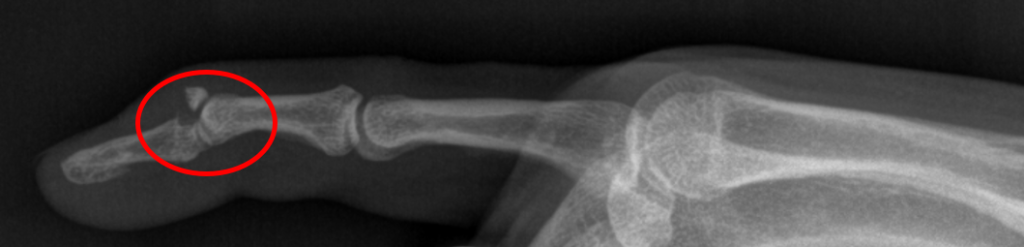

Πιο σπάνια, η παραμόρφωση αυτή μπορεί να συμβεί μετά από θλαστικό τραύμα, ενώ σε ορισμένες περιπτώσεις μπορεί να συνυπάρχει και αποσπαστικό κάταγμα στην κατάφυση του τένοντα. Τότε η πάθηση λέγεται οστικό (bony) Mallet finger.

Ο ασθενής με Μallet Finger χρειάζεται εκτίμηση από εξειδικευμένο Ορθοπαιδικό Χειρουργό. Ο κ. Βλάχος αφού λάβει το ιστορικό σας και σας εξετάσει πολύ προσεκτικά, θα σας παραπέμψει για μια απλή ακτινογραφία με σκοπό να αποκλειστεί η παρουσία ενός αποσπαστικού κατάγματος.